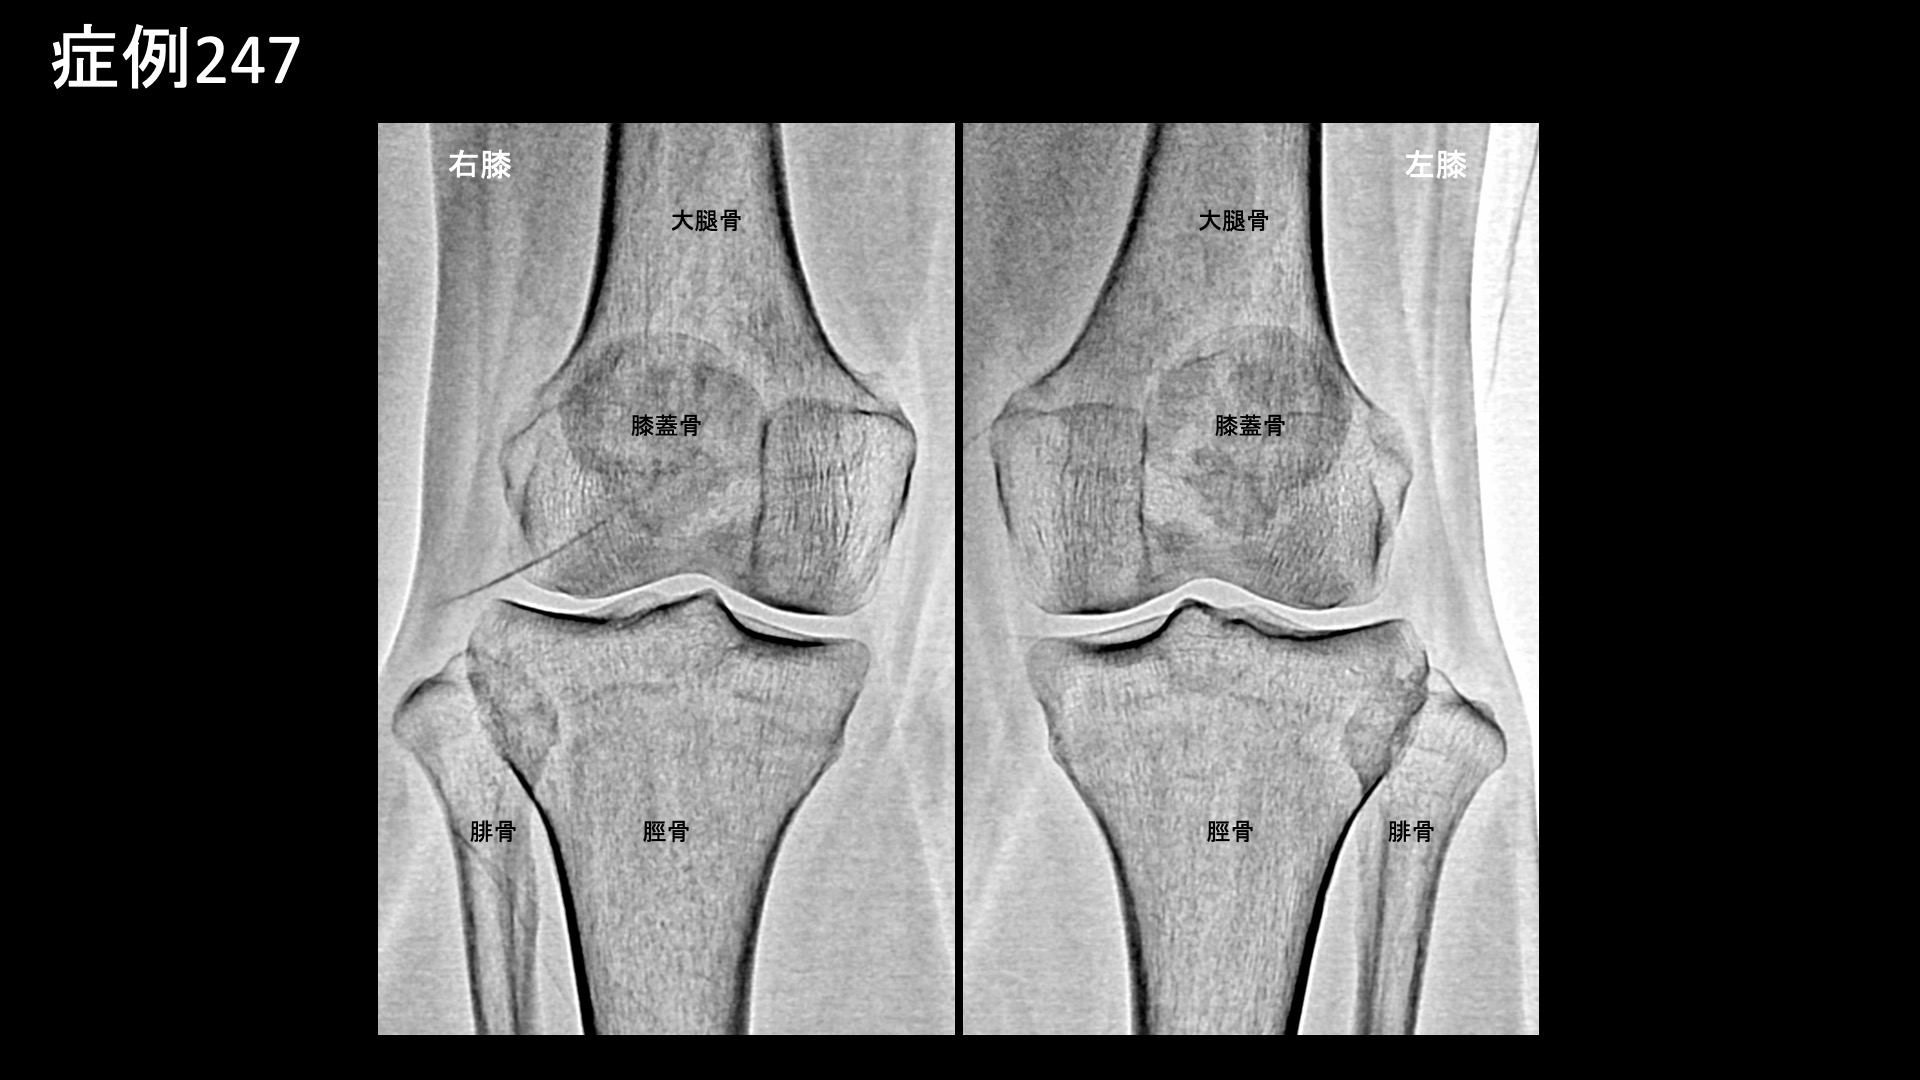

膝:変形性膝関節症など 【50代:女性】長い距離を歩くと痛くなる、登山家に生じた両膝の痛みに対するモヤモヤ血管治療(膝蓋下脂肪体炎、腸脛靭帯炎) 2025.11.05 鴨井院長による動画解説 受診までの経過 日常的に登山をされる方です。10年前に階段で転落してコンクリートの地面に両膝を打撲したことがありました。以前から、登山下山時に両膝が少し痛くなることがありましたが、1年半前頃に3-4時間程度の登山後に強い痛みがあったため、整形外科を受診しました。MRI検査の結果、軟骨の磨り減りはほとんど無く、膝蓋下脂肪体炎が疑われると言われました。2km以上歩くと痛くなり、その後2-3週間すると痛みが無くなります。3km以上になると、激痛になります。左右差は特にありませんでした。常に激痛があるわけではないものの、段々と歩ける距離が減ってきているため当院を受診されました。 診察時の所見 レントゲン、エコー検査とも変形性膝関節症の所見はありませんでした。膝蓋下脂肪体では、軽度の圧痛を認めました。MRIでも明らかな強い炎症ではありませんでしたが、両側膝蓋下脂肪体炎として矛盾せず、症状の性状からも治療による改善が期待されたため、モヤモヤ血管(病的新生血管)に対する運動器カテーテル治療(微細動脈塞栓術)を受けていただきました。 治療の所見 血管造影を行うと、両側の内側下膝動脈において、膝蓋下脂肪体に一致してモヤモヤ血管が濃染像として描出されました。更に左外側上膝動脈造影では、より豊富にモヤモヤ血管が濃染像として描出されました。術前の画像診断では明確ではありませんでしたが、症状の成因や、性状、この血管造影所見からは腸脛靭帯炎(代表的な、膝の外側の痛みの原因の一つ。別名ランナー膝。)の様相を呈していました。腸脛靭帯炎も合併していたのではないかと考えられます。治療後モヤモヤ血管は画像上速やかに消失しました。その他複数箇所の治療を行い終了しました。 治療前画像:損傷を受ける、あるいは繰り返しのストレスにより発生した異常な新生血管 治療後画像:カテーテルを用いて塞栓物質を血管内に投与し新生血管を塞いだ状態 治療費用:治療する部位によって費用が異なりますのでこちらをご参照ください。 主なリスク・副作用等:針を刺した場所が出血により腫れや痛みを生じたり、感染したりすることがあります(穿刺部合併症)。造影剤によるアレルギー(皮膚のかゆみ・赤み・息苦しくなるなどの症状)が出ることがあります。 治療後の経過 元々、少し長めに歩かなければ激痛は生じないため、治療後1ヶ月の直前に長めに歩いてみてもらいました。激痛は全く無く、階段を降りる際も、以前は他人の手を借りなければならなかったのが不要となっていました。まだ、熱い感じがしたり、それとは別に鈍い痛みを感じたりすることはありました。その後も順調に経過されたため、(良いことですが)受診はそれきりとなりました。追跡調査では、治療後3ヶ月時点で痛みは元の1/10程度、治療後6ヶ月ではほとんど痛みがゼロとなり、熱を持った感じも無くなりました。酷使して疲労が蓄積したときには鈍い痛みが出ることはありますが、それでも元の1/10程度とのことでした。膝蓋下脂肪体炎は比較的しつこい痛みの一つであり、完治するには少し時間がかかる傾向がありますが、ここまでくれば安心できます。無理のない範囲で登山を楽しんでいただければと思います。 膝蓋下脂肪体炎の詳細はこちら 【60代:女性】10年苦しんだ頭痛。考えがまとまらなくなり、家事もままならず。モヤモヤ血管治療により日常生活を取り戻すことができた実際の症例(筋緊張性頭痛、首肩こり、顎関節症) 前の記事 【60代:男性】痛くてドアノブも回せない、5年以上続いた手首の痛み。腱鞘炎に変形性手関節症を合併した一例(尺側手根伸筋腱の腱鞘炎、変形性手関節症、ドゥケルバン腱鞘炎) 次の記事